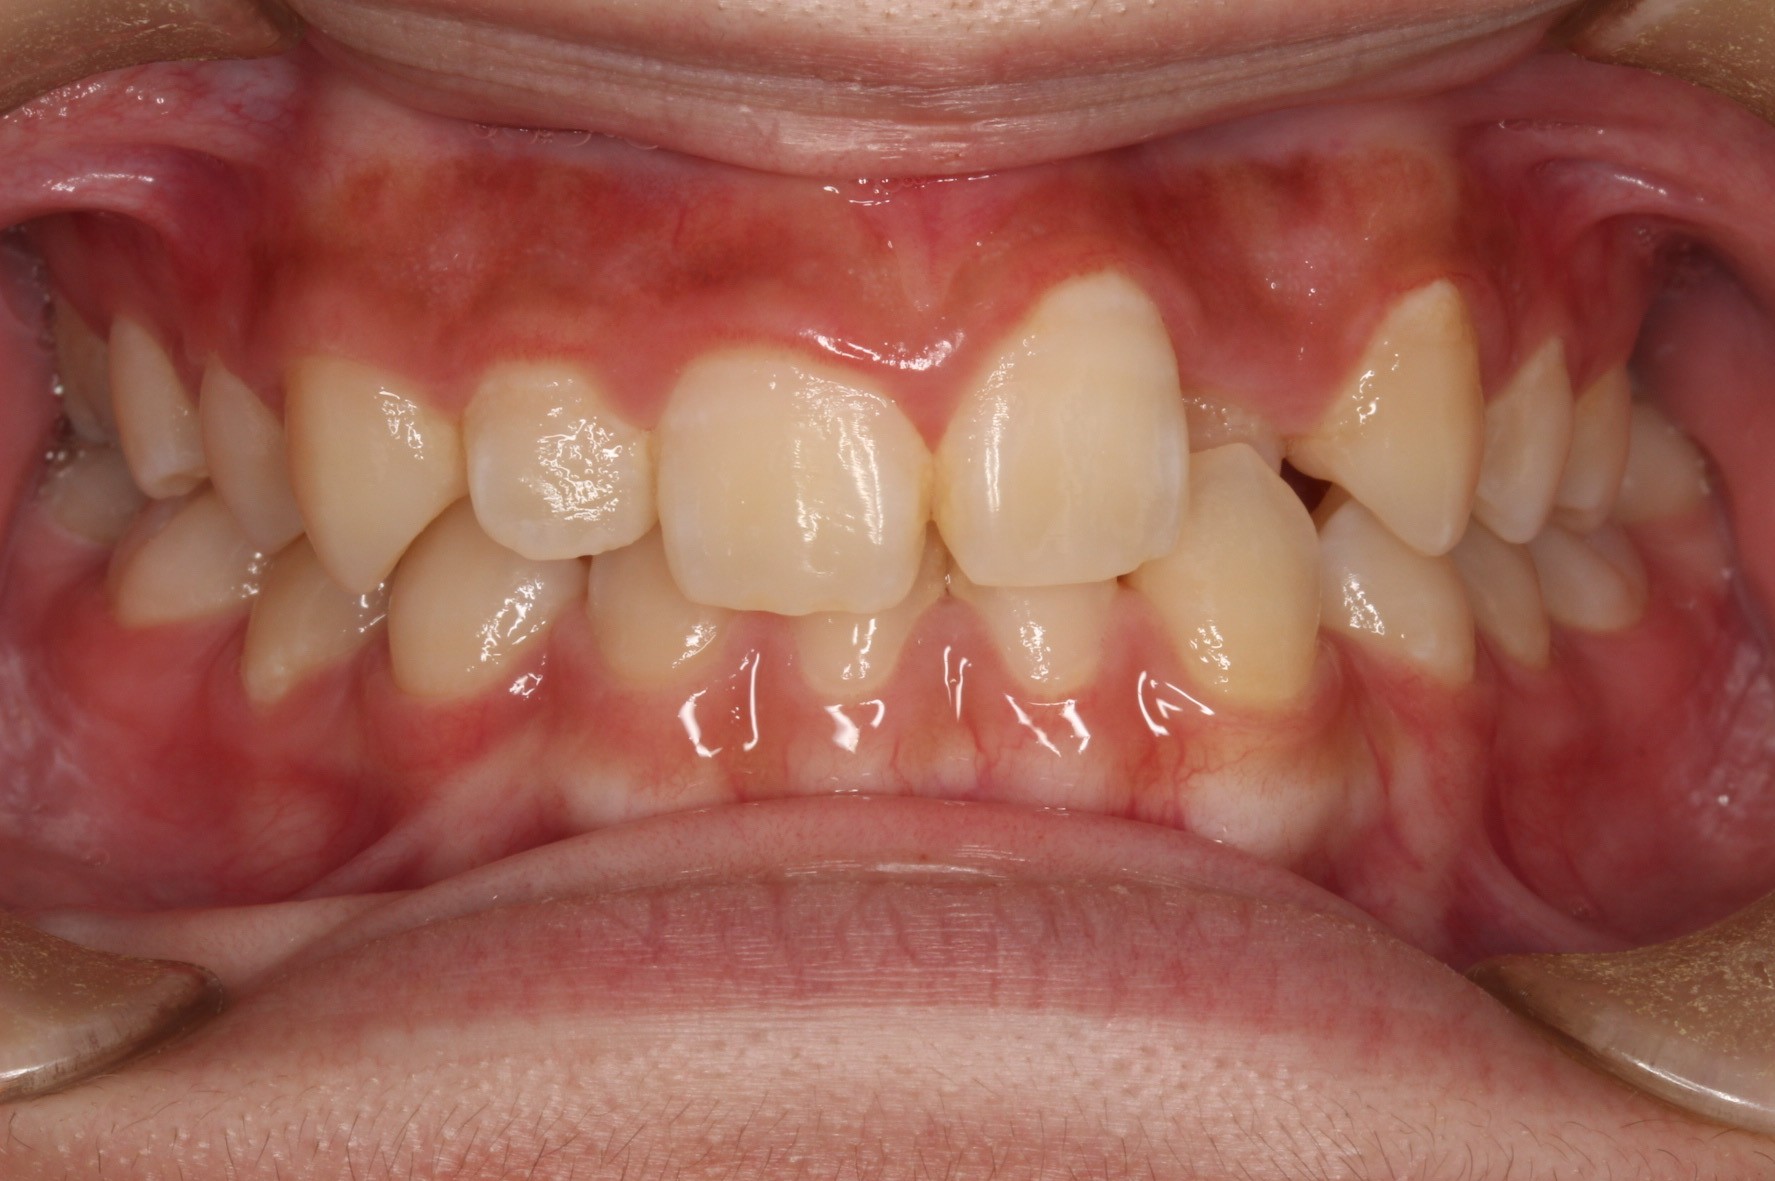

矯正術後:正面

今回ご紹介する患者様は、上の歯が1本だけ奥に引っ込んでいることを気にされており、矯正検査後Ⅱ級傾向の叢生と診断いたしました。

ワイヤー矯正後に、インビザラインによる仕上げ矯正を行っております。